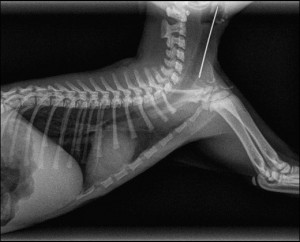

The shots are well developed instantly. In addition, in the event of fracture, including, If surgery is required, We can send by internet radios in our orthopaedic colleagues: they can view them and give us their opinion and a quote about the recommended surgery, in less than 24 hours most of the time.